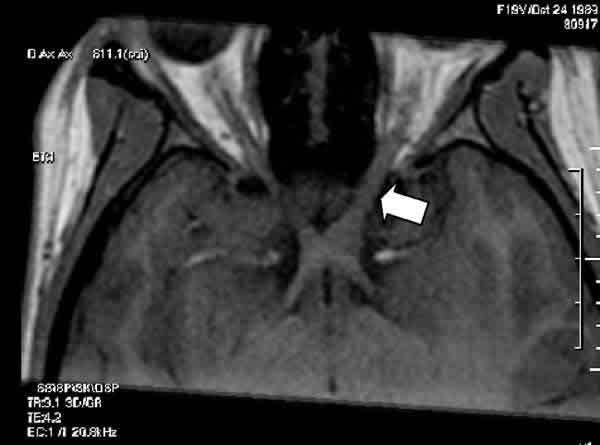

Una mujer de 20 años, con antecedentes de depresión mayor y ansiedad generalizada, acudió a consulta por pérdida de visión del ojo izquierdo (OI). La paciente refería que si bien la agudeza visual (AV) del OI había sido siempre muy baja, en los últimos meses notaba cierto empeoramiento visual. En la exploración, la AV del ojo derecho (OD) era de 1,0 (–4 –0,75 a 10º) y la del OI, 0,05 (–13,5 –4 a 5º). La exploración del segmento anterior sólo reveló una mínima opacidad subcapsular cristaliniana del OI. Funduscópicamente, se observaba una gran retinocoroidosis miopica en el OI. Se le diagnosticó de ambliopía profunda OI por anisometropía agravada por una catarata subcapsular incipiente en ese ojo. Se le remitió a Atención Primaria con la recomendación de revisiones oftalmológicas periódicas. Sin embargo, a los 4 meses, la paciente experimentó un cuadro autolimitado de alucinaciones auditivas («oía discusiones» y «voces que comentaban sus pensamientos»), por lo que fue valorada psiconeurológicamente. Al tratarse de síntomas atípicos de un trastorno afectivo, y para descartar un origen orgánico, se le realizó una resonancia magnética cerebral que evidenció la existencia de un engrosamiento de nervio óptico izquierdo localizado en su porción más posterior y en la región adyacente del quiasma óptico, muy sugestivo de glioma óptico (figs. 1 y 2). Reevaluada oftalmológicamente, la AV mejor corregida del OI se mantenía en 0,05, y la papila óptica del OI tenía un aspecto ligeramente pálido, difícil de valorar por las alteraciones miópicas (fig. 3). Campimétricamente, se objetivó una depresión generalizada del OI sin afectación del OD. La exploración neurológica no aportó ningún otro hallazgo, y en la dermatológica no se encontró ningún signo de neurofibromatosis tipo 1 (NF-1).

Fig. 1: En esta reconstrucción transversal en modo T1, se observa el engrosamiento del nervio óptico izquierdo (flecha) en la vecindad del quiasma.